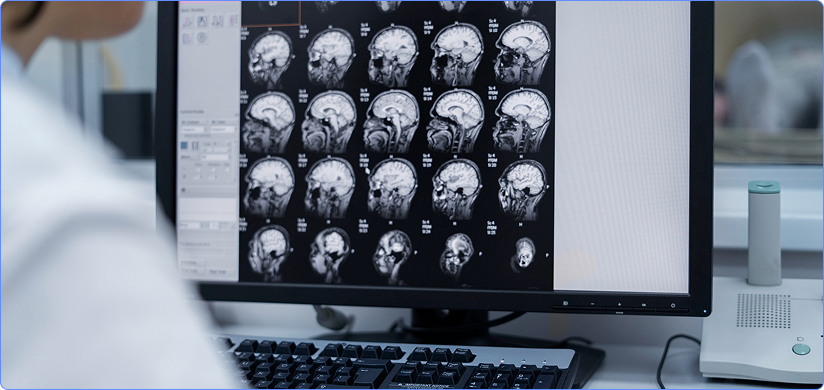

Brain CT Scan Reporting

Brain CT report is a diagnostic document written by radiologist help doctors diagnose brain related issues like injuries, severe headaches, dizziness, and other symptoms of aneurysm, bleeding, stroke, and brain tumors etc. A brain computed tomography (CT) scan is performed to observe the internal anatomical and vascular structures inside the human brain. It consists of several subcategories of imaging and is effective in the diagnosis of brain-related disorders, especially trauma, injuries, and tumors. Using expertise from a remote radiologist, brain CTs can be analyzed and interpreted in a timely manner.